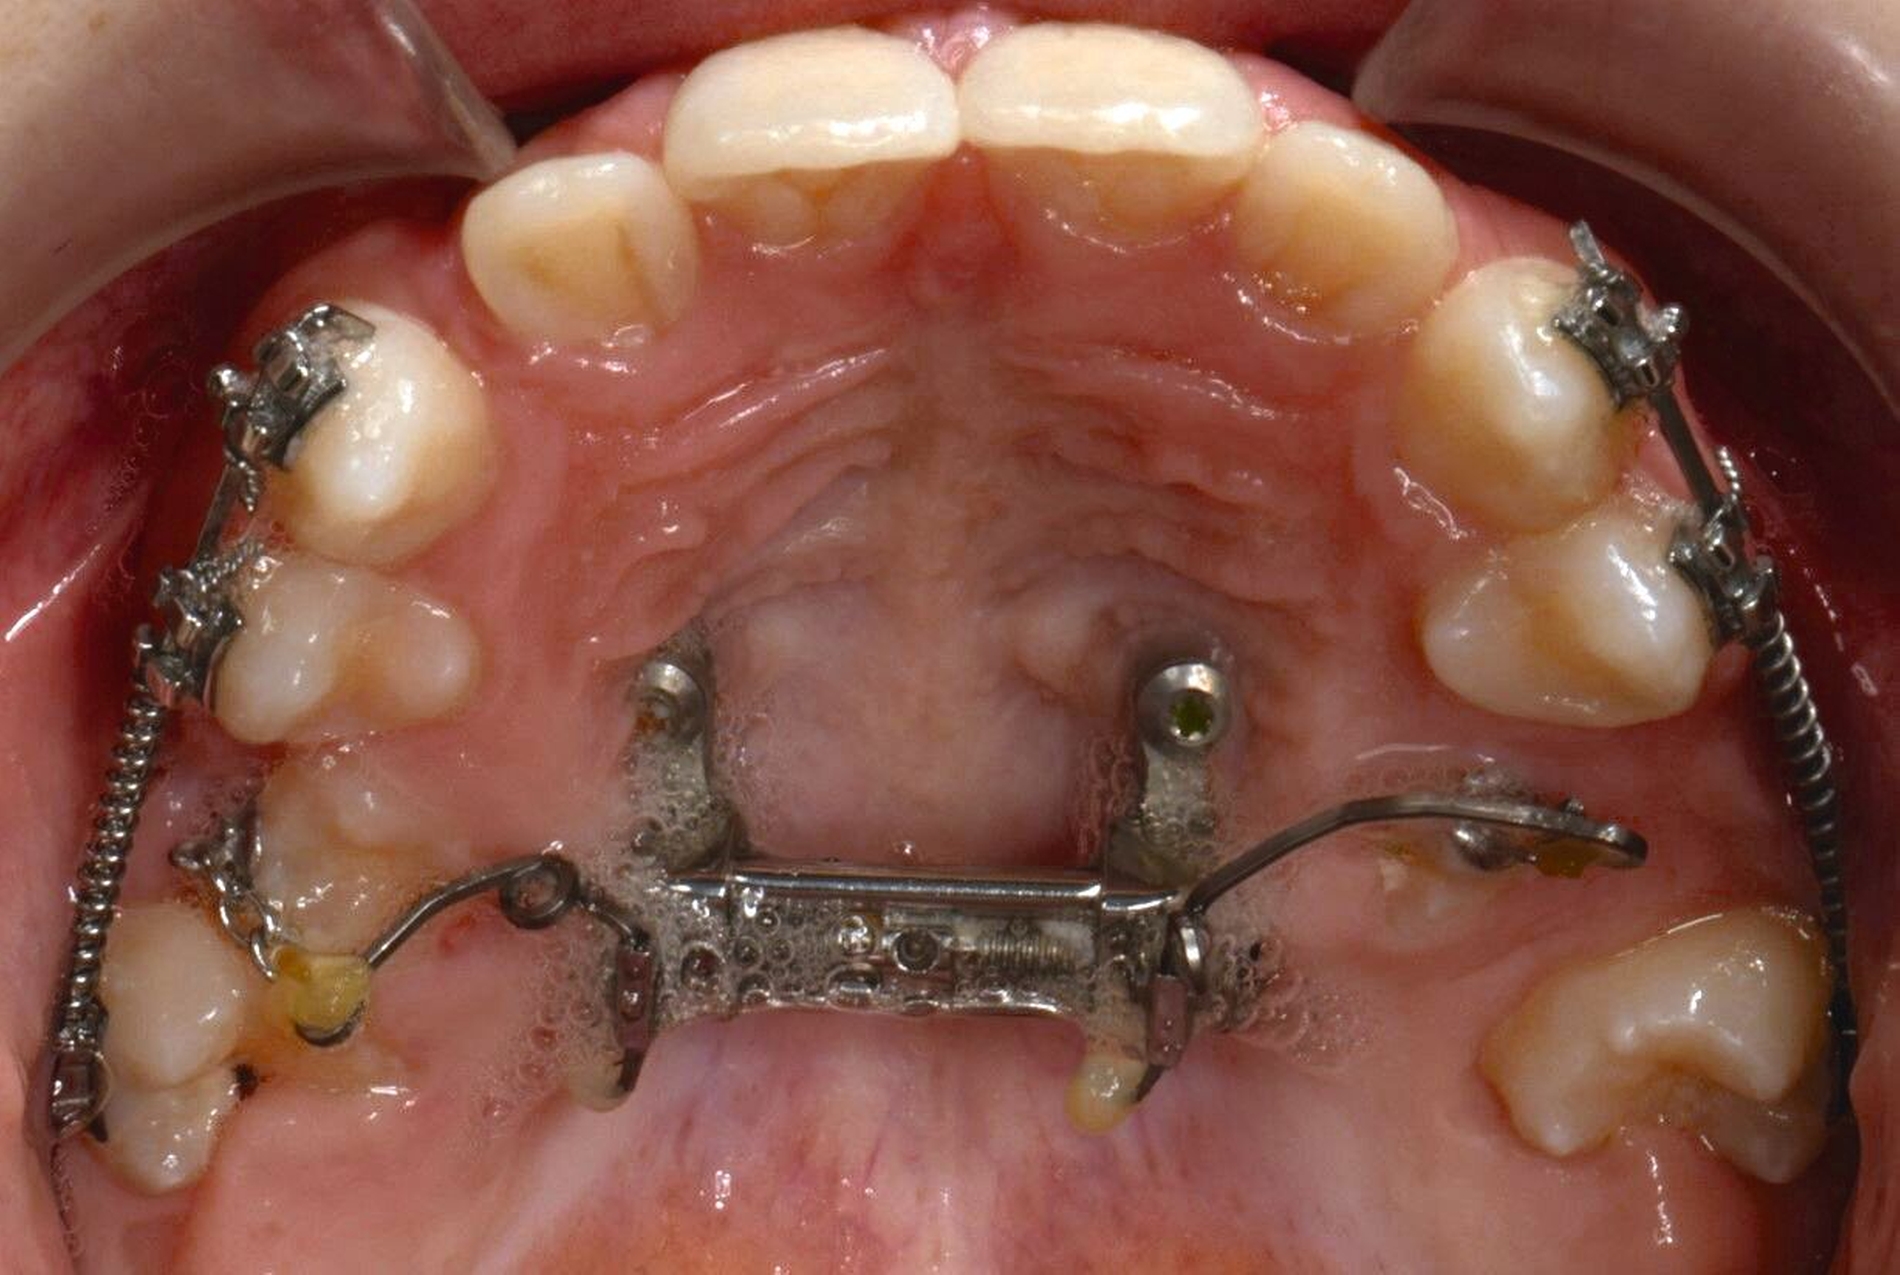

Für die Zähne 13, 16, 23 und 26 wurde eine weitere chirurgische Freilegung durchgeführt. Zwei Kragarme (0,017 x 0,025 Zoll TMA-Draht, Dentaurum, Ispringen, Deutschland) wurden verwendet, um die Zähne 13 und 23 kieferorthopädisch in den Zahnbogen einzustellen. Danach wurde eine Teil-Multi-Bracket-Apparatur eingesetzt, um die eruptierten Zähne zu nivellieren (Abbildung 5b). Nach einer Behandlungsdauer von circa sechs Monaten waren die chirurgisch freigelegten Zähne optimal eingeordnet (Abbildungen 5c und 5d). Um die Lücke für die noch retinierten Prämolaren 15 und 25 zu öffnen, wurden in dieser Region auf den Teilbögen offene Federn angebracht. Danach wurden die Zähne 15 und 25 chirurgisch freigelegt und ebenfalls mithilfe von zwei Kragarmen (0,017 x 0,025 Zoll TMA-Draht) eingestellt (Abbildungen 5e und 5f, Abbildung 6).

Das Endergebnis ist in der Panoramaschichtaufnahme in Abbildung 6 gezeigt, in der beide Mini-Implantate keine Anzeichen einer periimplantären Osteolyse aufweisen. Während des Behandlungszeitraums von insgesamt 31 Monaten wurden keine unerwünschten Nebenwirkungen beobachtet.